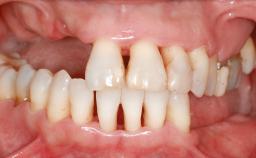

Iliac and Calvarial Bone Blocks for Onlay Grafting of a Severely Resorbed Edentulous Maxilla

A 45-year-old woman with a completely edentulous maxilla was referred to evaluate the possibility of rehabilitation with an implant-supported prosthesis. This patient was healthy and a non-smoker. She had been wearing a maxillary complete denture opposing a natural mandibular dentition since her twenties. This situation had resulted in progressive resorption of the alveolar ridge, repeatedly creating a need for relining the denture. Twenty years later, despite multiple adaptations and the use of “glues” the denture was unstable and causing the patient psychological and functional discomfort.

Bone Volume Horizontally and vertically sufficient Horizontally deficient Deficient vertically or deficient vertically AND horizontally

Bone Volume Deficient vertically or deficient vertically AND horizontally

Defining Characteristics Fully edentulous upper jaw to be rehabilitated with an implant-borne fixed dental prosthesis